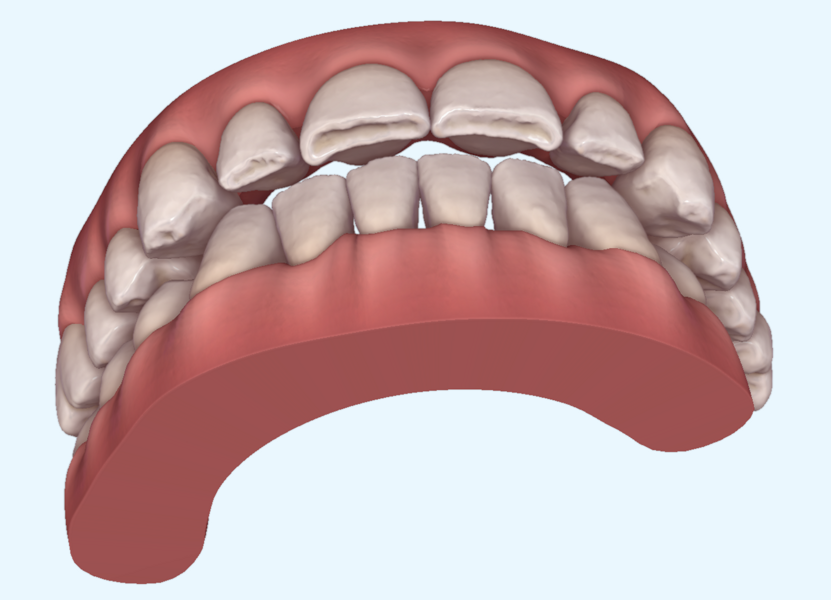

Tongue posture alteration, atypical swallowing and perioral muscle dysfunction from birth result in the development of jaw and dental dysmorphism. The masticatory muscles then reinforce functional alteration. Once altered during development, the oral cavity grows, matures and ages, progressively worsening the peculiar and groupable morphotypes (Figs. 1–5).

This patient, like all patients requiring interdisciplinary rehabilitation, had to first undergo periodontal treatment and caries restoration (Fig. 17). At the same time, it was important to rehabilitate swallowing with Froggymouth and relax the masticatory muscles and relieve the TMJs with an occlusal device. We could then study the orthodontic treatment plan using Invisalign ClinCheck (Align Technology) and showed the treatment plan to the interdisciplinary team and to the patient (Fig. 18). We were then able to create the correct sequence of orthodontic treatment, bone augmentation and implant surgery needed for the posterior edentulous spaces.

After the first phase of aligner treatment, we had achieved better inter-arch coherence, better maxillary arch expansion, and some space for improving the anterior tooth proportions restoratively (Fig. 19). We then temporarily restored the anterior teeth directly with composite, closing the spaces, improving the tooth proportions and further increasing the maxillary arch expansion (Fig. 20). We used restorative arch expansion to reduce the orthodontic destabilisation of the teeth to achieve the correct inter-arch coherence and retain the teeth in the cortical bone.38 A refinement aligner phase was undertaken to improve the final alignment of the gingival zenith and to improve the inter-arch coherence (Fig. 21). The periods of the first orthodontic phase and of the refinement were used to augment the mandibular and maxillary bone and to place the implants (Fig. 22). At the end of the orthodontic treatment, the case was finalised with ceramic veneers in the anterior area and temporary restorations on the implants in the posterior area (Figs. 23–26).